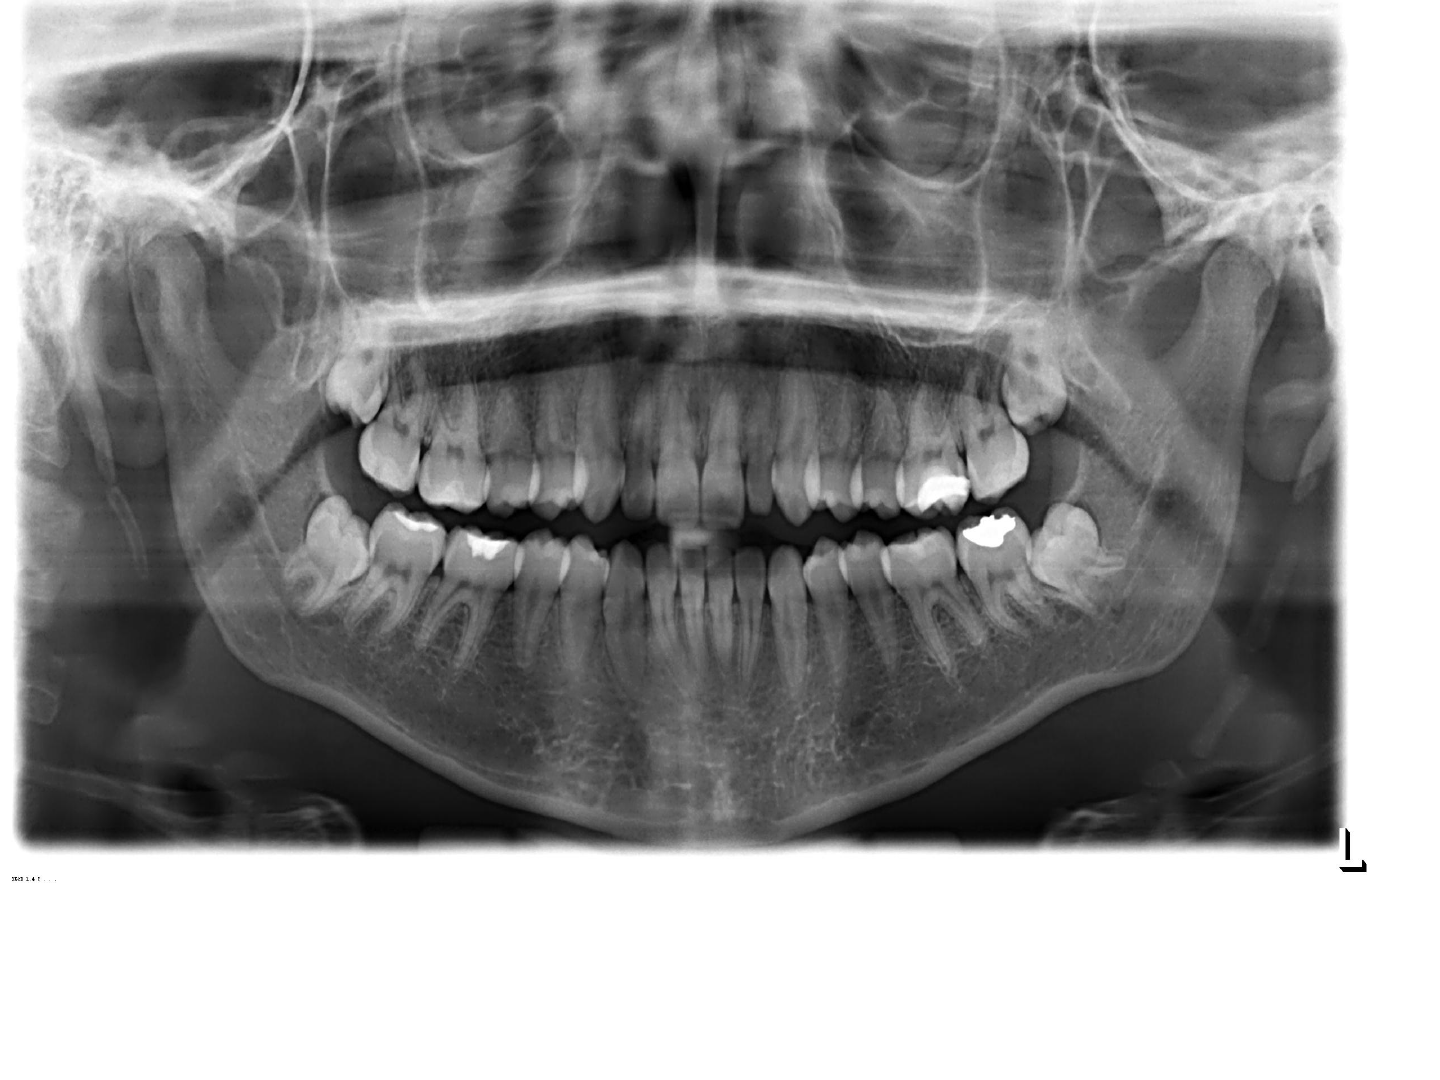

Espinha Nasal Anterior

Palato duro

Fossas Nasais

Septo Nasal

5. Órbitas

6. Seios Nasais

7. 3º molares inclusos

8. Processo Condilar da Mandíbula

9. Canal Mandibular

Linha Oblíqua Externa

Forame Mentual

12. Conchas Nasais

13. Base da Mandíbula

14. Fóvea Mandibular

15. Processo Estilóide

Discrição dos aspectos anatômicos radiografados

Seio Maxilar – Imagem radiolucida delimitada por uma area radiopaca, se estende da região de canino (parte anterior do seio) o assoalho bem próximo as raízes dos pré-molares e molares.

Palato duro – Linha horizontal radiopaca localizada acima das raízes dos dentes superiores.

Orbita – Imagem radiolucida de forma oval, localizada acima do seio maxilar, estar próximo ao seio maxilar.

Septo Nasal – É uma imagem radiopaca na vertical que Separa a fossa nasal em duas imagens radiolucidas.

Espinha nasal anterior: É uma imagem radiopaca em forma de V localizada acima dos ápices dos incisivos centrais superiores

Concha nasal : apresenta-se como uma imagem radiopaca convexas localizada no interior das fossas nasais.

Processo zigomatico da maxila: apresenta como uma imagem radiopaca espessa localizada acima dos molares superiores.

Forame mentual: imagem radiolucida de tamanho pequeno, de formato arredondado localizado na areaperiapical dos pre molares inferiores.

Canal mandibular: apresenta-se como uma faixa radiolucida delimitada por duas linhas radiopacas. Se estende desde o forame mandibular até o forame mentual.

Base da mandíbula: apresenta-se como uma faixa radiopaca densa que representa o contorno inferior da mandibula.

Fovea submandibular: apresenta-se como uma imagem radiolucida ampla na região de molares inferiores, bilateral.

Linha oblíqua : apresenta-se como uma linha radiopaca densa que se estende anterior e inferiormente a partir da borda anterior do ramo da mandíbula em uma posição superior e paralela a linha milo hioidea.